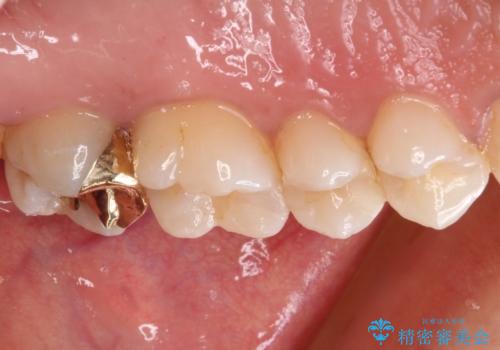

ゴールドインレーは銀歯のインレーやセラミックインレーと比べ、「技工操作の精度が高く、適合が著しく良い」というメリットがあります。特に上の奥歯は歯科医師の操作が行いにくいため、「適合の良さ」は再治療のリスクを防ぐ上でとても重要な要素となります。

上の奥歯は金属色が見えることもないため、審美的な問題は全くありません。

咬み心地はとても良好で、全く違和感がなく、患者様には大変満足していただきました。